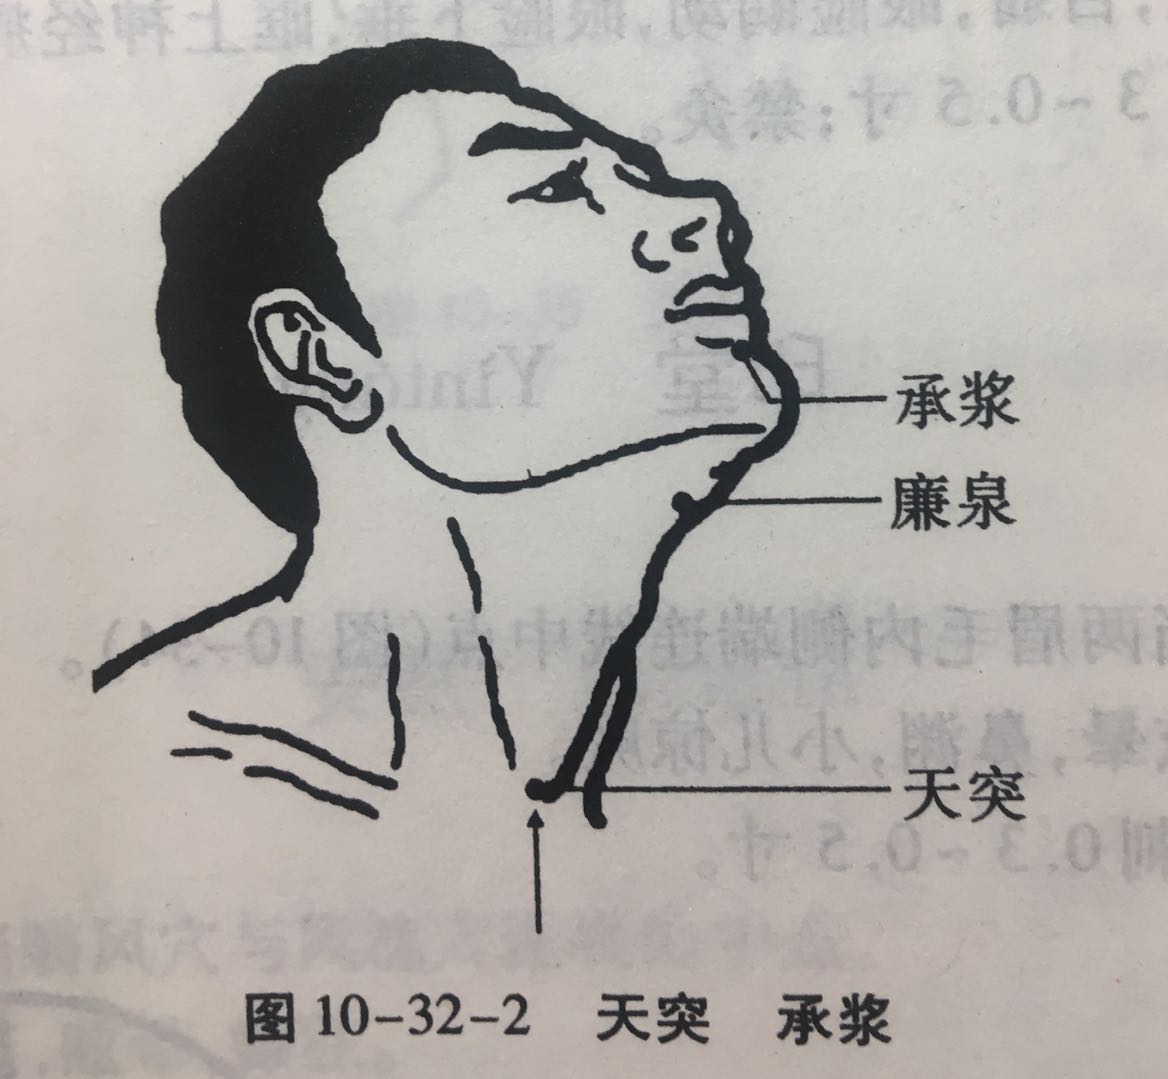

天突

【定位】 在颈部,当前正中线上胸骨上窝中央(图 10-32-2)。

【主治】 咳嗽,哮喘,胸中气逆,咯唾脓血,咽喉肿痛,舌下急,暴喑,瘿气,噎嗝,梅核气。

【配伍】 配定喘穴、鱼际治哮喘、咳嗽,配膻中、列缺治外感咳嗽,配内关、中脘治呃逆,配廉泉、涌泉治暴喑,配丰隆治梅核气,配少商、天容治咽喉肿痛,配气舍、合谷治地方性甲状腺肿大。

【刺灸法】 先直刺 0.2 ~ 0.3 寸,然后沿胸骨柄后缘,气管前缘缓慢向下刺入 0.5 ~ 1 寸;可灸。

【附注】 阴维、任脉之会。

【注意】 本穴针刺不能过深,也不宜向左右刺,以防刺伤锁骨下动脉及肺尖。如刺中气管壁,针下有硬而轻度弹性的感觉,病人出现喉痒欲咳等现象;若刺破气管壁,可引起剧烈的咳嗽及血痰等现象。如刺中无名静脉或主动脉弓时,针下可有柔软而有弹力的阻力或病人有疼痛感觉,应即退针。

承浆

【定位】 在面部,当颏(kē)唇沟的正中凹陷处(图 10-32-2)。

【主治】 口眼歪斜,唇紧,面肿,齿痛,齿衄,龈肿,流涎,口舌生疮,暴喑不言,消渴嗜饮,小便不禁,癫痫。

【配伍】 配委中治衄血不止,配风府治头项强痛、牙痛。

【刺灸法】 斜刺 0.3 ~ 0.5 寸;可灸。

【附注】 足阳明、任脉之会。